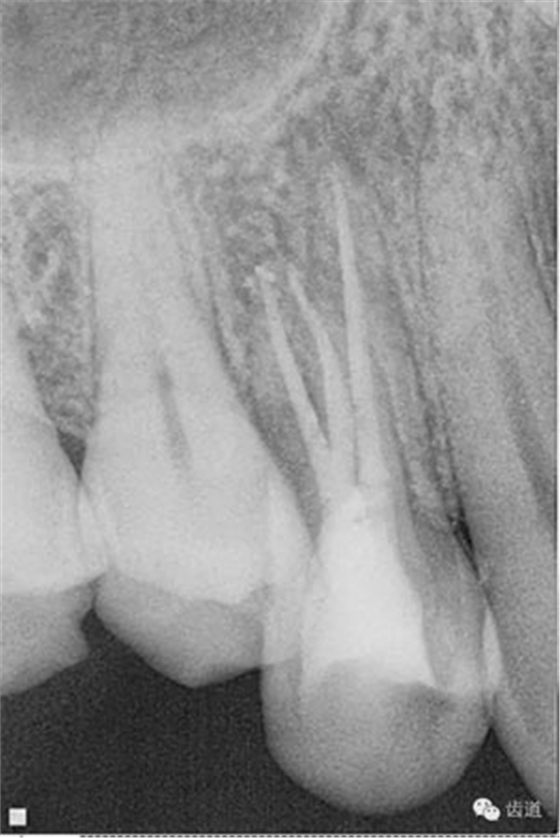

數(shù)碼x攝影顯示:近中頰根及腭根根管充填恰填,遠(yuǎn)中根管有遺漏。

檢查顯示:近頰及腭根充填恰填,遠(yuǎn)頰根管內(nèi)有少許充填物影像。根尖明顯低密度影像。

處理:顯微根管治療。放置橡皮障,去除暫封,顯微鏡下超聲去除頰側(cè)根管上段部分牙本質(zhì),探及遠(yuǎn)中根管口,見(jiàn)有糊劑遮蓋。Pathfile根管疏通,MTwo根管預(yù)備至2506#,配合3%次氯酸鈉和17%EDTA超聲蕩洗,干燥根管,放置氫氧化鈣糊劑,zoe暫封。

處理:放置橡皮障,去除暫封,超聲結(jié)合2%CHX清除遠(yuǎn)頰根管內(nèi)氫氧化鈣糊劑,主牙膠試合后95%酒精沖洗干燥根管,結(jié)合AHPlus糊劑連續(xù)波熱牙膠垂直加壓充填根管,樹(shù)脂分層粘接修復(fù)牙體。建議定時(shí)復(fù)診進(jìn)行嵌體修復(fù),患者未執(zhí)行。